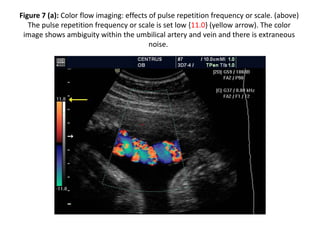

Figure 7 (a): Color flow imaging: effects of pulse repetition frequency or scale. (above)

The pulse repetition frequency or scale is set low {11.0} (yellow arrow). The color

image shows ambiguity within the umbilical artery and vein and there is extraneous

noise.